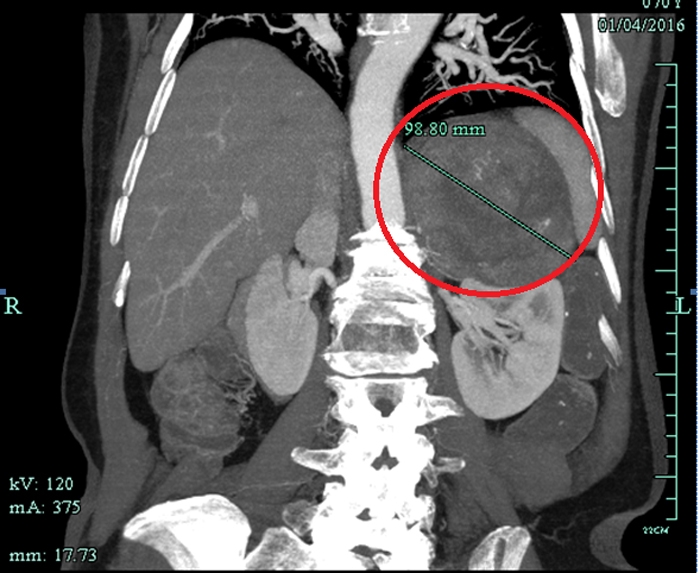

CT檢查意外發(fā)現(xiàn)巨大腫瘤

??? 原來,朱老太與高血壓相伴已經(jīng)有20多年了,一直服用降壓藥,而且血壓忽高忽低不穩(wěn)定。一個多月前,因為重癥肺炎在當(dāng)?shù)蒯t(yī)院住院,行胸部CT檢查的時候發(fā)現(xiàn)左上腹有一個十多公分的巨大腫瘤。家人馬上把朱老太送到省城一家大醫(yī)院住院,磁共振檢查后考慮左腎上腺惡性腫瘤,需要做大手術(shù)。家人擔(dān)心老人瘦弱的身體承受不了開腹手術(shù),多方打聽后得知市人民醫(yī)院泌尿外科做腹腔鏡手術(shù)技術(shù)成熟,就找到了萬里軍醫(yī)師。萬醫(yī)生初步診斷為左腎上腺嗜鉻細(xì)胞瘤,考慮是惡性腫瘤,雖然腫瘤體積巨大,但能在腹腔鏡下切除腫瘤。

患者CT影像

??? 萬里軍仔細(xì)看了CT和磁共振片后,認(rèn)為腫瘤與腎靜脈、腹主動脈關(guān)系密切,建議用衢州市人民醫(yī)院最新引進(jìn)的320排螺旋CT做個血管成像,明確腫瘤與這些重要血管的關(guān)系。同時啟動了多學(xué)科會診治療(MDT)程序,邀請呼吸內(nèi)科、心血管內(nèi)科、內(nèi)分泌科、麻醉科、重癥醫(yī)學(xué)科、輸血科等相關(guān)科室進(jìn)行會診,充分估計術(shù)前、術(shù)中和術(shù)后可能遇到的問題,制定了幾套方案。與患者及家屬進(jìn)行溝通,獲得他們的配合信任。